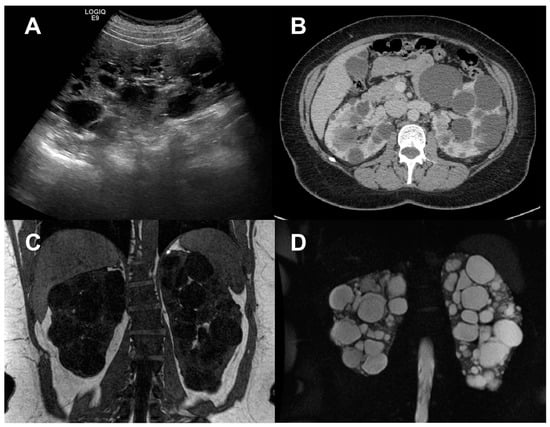

As renal enlargement is the underlying macroscopic process, ultrasonography (US), computerized tomography (CT), and magnetic resonance imaging (MRI) have been used for many years to quantify kidney disease progression in ADPKD (Figure 1) [3,7,8,9,10], recently allowing us to also investigate the relationship between the kidney or cyst volume increase, and renal function decline in the polycystic kidney [11,12,13].

Figure 1.

Anatomical imaging of the polycystic kidney. Representative B-mode US image (A), contrast-enhanced CT image (B), and anatomical MRI, obtained via T1-weighted (C) and T2-weighted (D) sequences in human patients with autosomal dominant polycystic kidney disease. All techniques illustrate the presence of enlarged echogenic kidneys, and fluid-filled cysts in the kidney parenchyma.